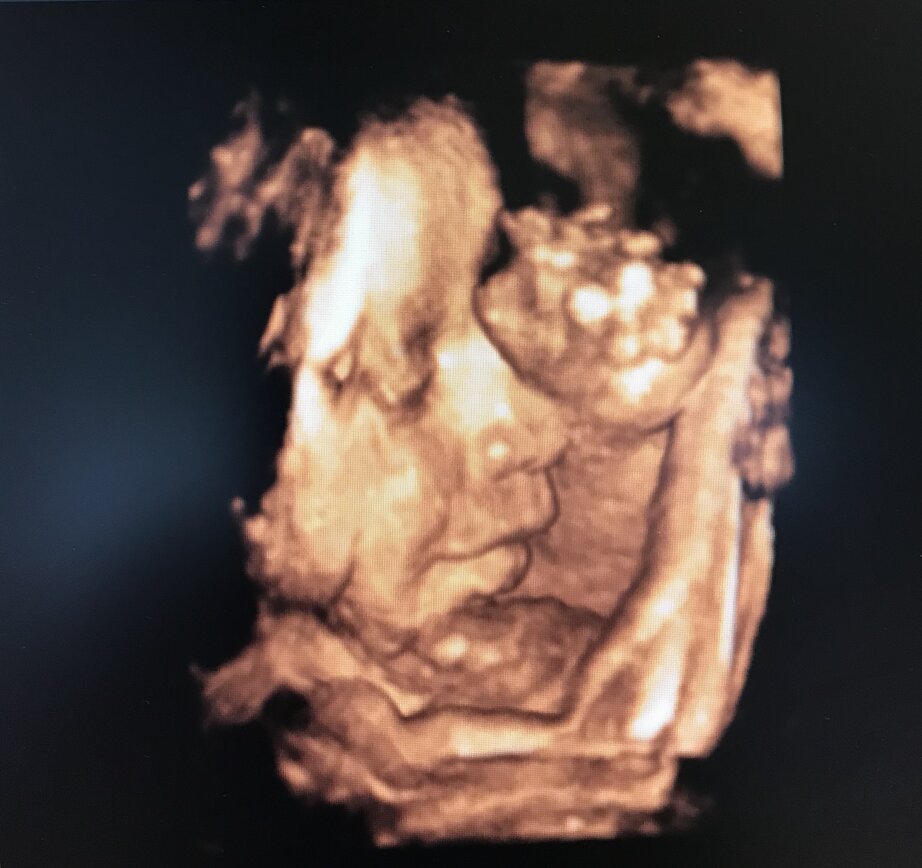

ECOGRAFIA 3D 4D